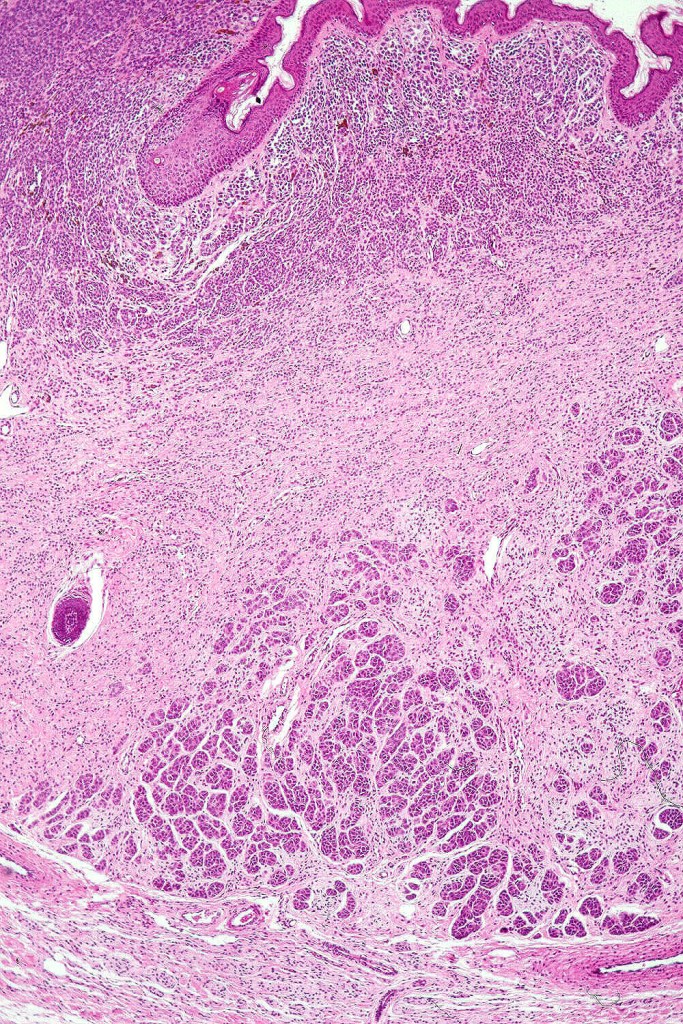

Histological features

•The nodule generally merges with the adjacent nevus but sometimes it can be sharply circumscribed

•It is hypercellular and most often composed of epithelioid cells showing little pleomorphism & only occasional mitoses

•Nuleoli are small

•Intracytoplasmic pseudo-inclusions

•The constituent cells are generally larger than the adjacent nevus cells

•Some examples show more marked pleomorphism with prominent nucleoli and increased mitotic activity but abnormal mitoses are not a feature. These are not associated with any sinister biological potential

•Absence of necrosis, hemorrhage or Pagetoid spread in the overlying epidermis

•Spindle cell, small blue cell, blue nevus-like features, Spitzoid & proliferative nodules with mesenchymal differentiation (myofibroblastic, chondroid & osteoid) can be seen